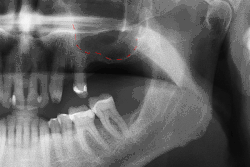

X-ray showing a sinus lift in the left upper jaw

Before undergoing sinus augmentation, diagnostic tests are used to determine the health of the patient's sinuses. Panoramic radiographs are taken to map out the patient's upper jaw and sinuses. In special instances, cone beam computed tomography is preferable in measuring sinus height and width, ruling out any sinus disease or pathology.[7]